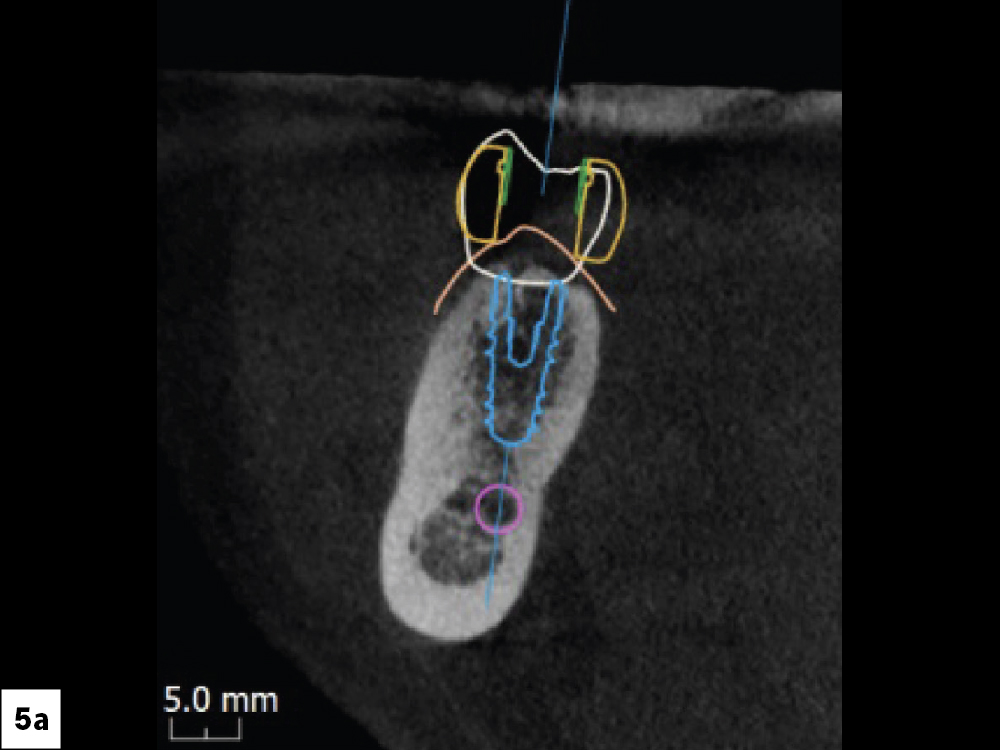

Occlusal View Which Indicates the Placement of the Surgical Guide

Detailed Surgical Report Revealing Distance to Vital Structures

Figures 5a, 5b: An occlusal view clearly indicated the placement of the surgical guide and confirmed the trajectory the implant would follow as well as the position of the access hole on the occlusal surface. The detailed surgical report included a cross section revealing the implant’s proximity to vital structures. I could see the outline of the crown, the access channel, the outline of the implant (in blue), and the inferior alveolar nerve canal (in purple). I noted the distance between the implant and the nerve canal as well as the lingual concavity, another very important landmark when placing implants. To avoid complications, the plan maintained a safety zone of at least 2 mm.